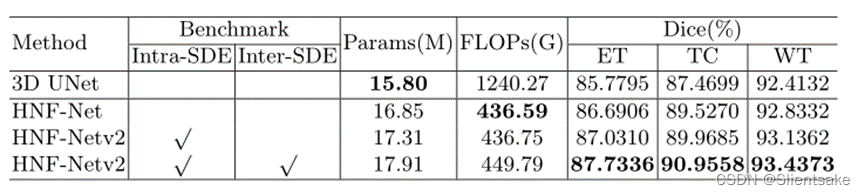

为了评估在HNF-Netv2中提出的SDE块的有效性,作者首先使用五倍交叉验证对训练集进行消融研究。作者选择3D U-Net作为基线模型。此外,作者先后测试了原始HNF-Net的性能,使用了尺度内的SDE块,并进一步测试了尺度内的SDE块(提议的HNF-Netv2)。如表1所示,通过Dice评分和对分割性能进行评价

表1:BraTS 2021训练装置的消融研究。Inter-SDE:尺度间SDE块,Intra-SDE:尺度内SDE块,DSC:骰子相似系数,HD95: Hausdorff距离(95%),WT:整个肿瘤,TC:肿瘤核心,ET:增强肿瘤核心。